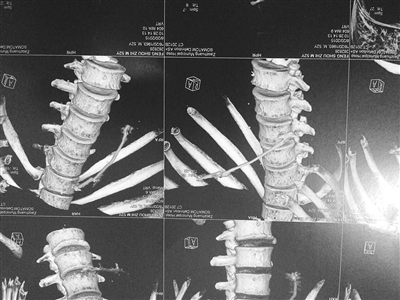

对冯某进行体检时,体内发现异物

取出的铁丝

据介绍,冯某和徐某之前就曾多次因为砸车盗包被公安机关处理。近日,其中的一名犯罪嫌疑人冯某自知难逃罪责,在被抓捕前三天吞下铁丝。警方抓捕后在对冯某进行体检时,在其体内发现异物,遂将其取出。